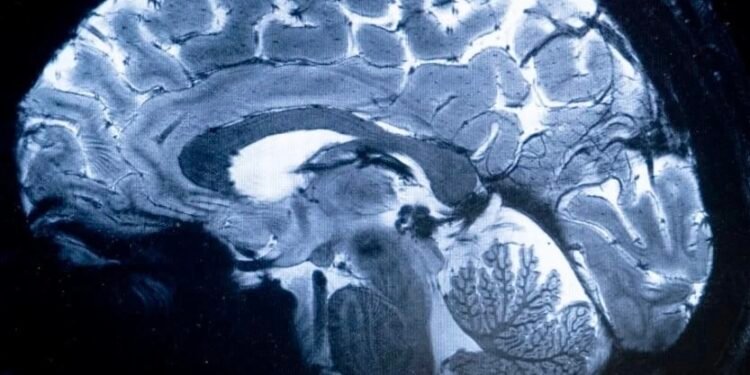

نجح فريق دولي من الباحثين، في جامعة ماكجيل الكندية، في العثور على موقعين بالدماغ تظهر فيهما نقطة البداية لمرض الفصام بالدماغ، للمرة الأولى، وهما منطقة “بروكا والقشرة الجبهية الجزيرة”، ما يجعل تشخيص بداية الاضطراب العصبي أسهل من خلال فحص الدماغ بالرنين المغناطيسي القياسي.

وبحث فريق الباحثين، في الجامعة، باستخدام عملية تحليلية جديدة تُعرف باسم “رسم خرائط المركز”، عن أوجه التشابه والاختلاف بين عمليات مسح الدماغ لـ 1124 شخصا مصابا بالفصام، و1046 شخصا من الأصحاء.

وأشارت معطيات الدراسة، إلى أن المرض يمكن أن ينشأ بمجموعة متنوعة من المناطق، إلا أن التشوهات في بنيتين بالدماغ لهما روابط ثابتة باللغة والمعالجة العاطفية، برزت على أنها كبيرة.

وصرحت لينا بالانيابان، من جامعة ماكجيل قائلة: “يخبرنا هذا أن كل شخص يعاني هذه الحالة لديه نقطة بداية فريدة قد تفسر الاختلافات في الأعراض، ولكن هناك عملية مشتركة تؤدي إلى تغييرات أكثر انتشارا، وإن كانت دقيقة، في بنية الدماغ”.